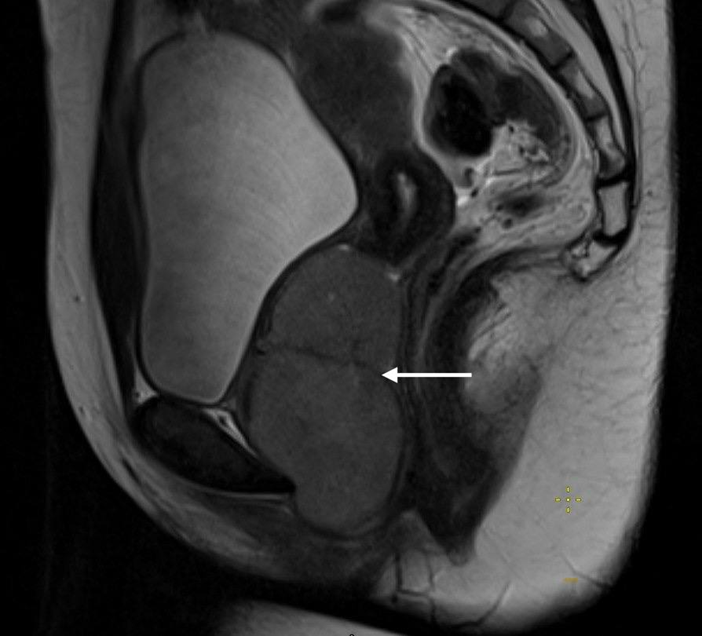

Contrast-enhanced MRI of the pelvis: The uterus is anteflexed, not enlarged: 50x45x53 mm. The cavity is not enlarged, the endometrium is homogeneous. The right ovary measures 32x24x26 mm and contains a moderate number of follicles. The left ovary measures 53x42x38 mm and is enlarged due to two cystic formations measuring 32.5x25x23 mm and 13.5x12.5x11 mm. In the vaginal lumen, on the anterior and right walls, two solid formations with a fairly homogeneous internal structure are determined, with a clear capsule, smooth contours, measuring 51x59x40.5 mm and 42x37x55.5 mm, with pronounced diffusion restriction. The latter formation is closely adjacent to the cervix without signs of infiltration. After the introduction of a contrast agent, its uneven accumulation in the formations is determined. Conclusion: MR image of two large solid formations in the pelvic-perineal region. MR data of focal formations of the left ovary of the endometrioid cyst type (Figs. 1 and 2).

Figure 1: MRI image of a sagittal section of the small pelvis.